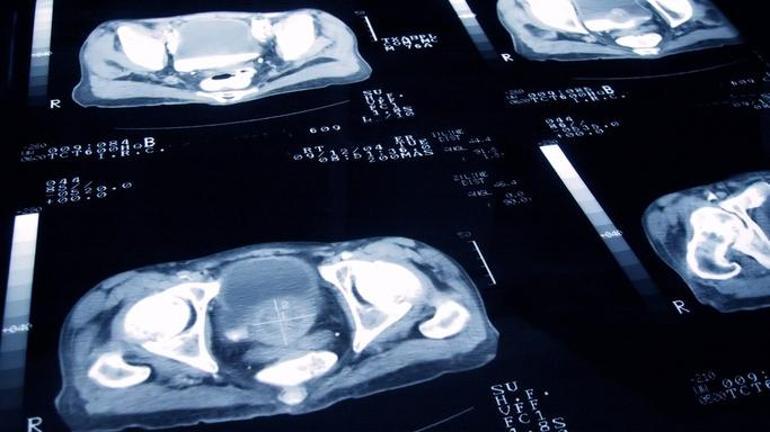

Erkeklerde en yaygın kanser türü olan prostat kanserinde erken tanı artık çok daha mümkün olmuştur. Yakın zamanda geliştirilen teşhis yöntemleri sayesinde, hastalık semptomların ortaya çıkması olmadan teşhis edilebilir. Bu, işleme sürecindeki başarı oranını arttırır. Sinsi olan prostat kanseri, herhangi bir semptom olmadan uzun süre gelişebilir. Bununla birlikte, gelişmekte olan MR teknolojisi sayesinde, tümör daha önce fark edilebilir.

“Prostat kanseri çok sinsi bir hastalıktır, çünkü ilerleme sırasında herhangi bir semptom sağlamaz. Bununla birlikte, ayrıntılı görüntüleme sağlayan MR teknolojileri sayesinde, şimdi prostat kanserini daha net görebiliriz, ilk aşamayı teşhis edebiliriz. Bu, tedaviye daha önce başlamamıza izin verir.

Geçmişte, şüpheli bir durum olduğunda rastgele alanlardan örnekler alıyorduk. Yürüyüş alanını bir turuncu bulma girişimi olarak düşünebiliriz. Bununla birlikte, manyetik rezonans görüntüleme sayesinde, şüpheli bölge doğrudan tespit edilir ve sadece o bölgede biyopsi ile teşhis edilir.

Klasik yöntemlerden farklı olarak, tüm prostat bezine değil, sadece tümör bölgesine müdahale ediyoruz. Bu şekilde, ikimiz de tanıyı daha önce koyduk ve hastaya daha rahat ve etkili bir tedavi sunuyoruz. “